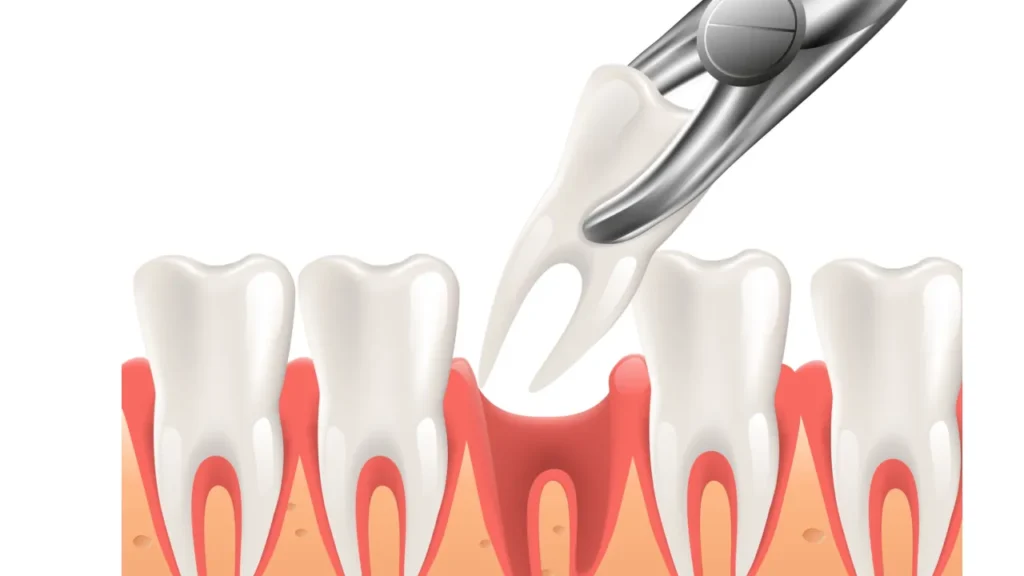

What is the procedure for a tooth extraction?

Your tooth extraction will either be simple or surgical, depending on whether your tooth is visible or impacted.

Simple extraction

You will receive a local anesthetic, which numbs the area around your tooth so you’ll feel only pressure, not pain, during the procedure. The dentist then uses an instrument called an elevator to loosen the tooth and forceps to remove it.

Surgical extraction

You will likely receive both local anesthesia and intravenous anesthesia, the latter of which makes you calm and relaxed. You may also receive general anesthesia, depending on any medical conditions. With general anesthesia, you will remain unconscious during the procedure.

The general dentist or oral surgeon will cut into your gum with a small incision. They may need to remove bone around your tooth or cut your tooth before it can be extracted.